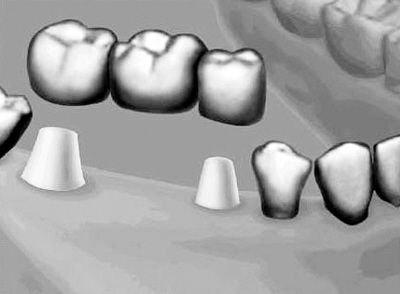

2、固定牙修复

利用缺牙两侧的牙齿作为基牙,通过牙体预备用烤瓷冠或金属冠修复。假牙不能自由摘戴。假牙与天然牙(真牙)大小和外形及色泽相似,戴用舒适美观且咀嚼功能恢复好。由于要磨除牙体较多,很多顾客不愿接受这种修复方式。固定修复需18周岁以上。一般在牙齿拔除后3个月修复。